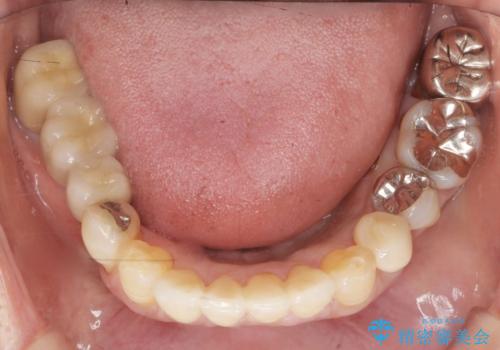

前歯がかけた、ぐらぐらする 60代女性

- 下の前歯が欠けてぐらぐらすることを主訴に来院された患者様です。

以前行った奥歯の治療により下顎前歯の動揺は改善傾向にあり顕著ではなかったのですが、欠けて黒くなっていることと少しの動揺が気になるとのことでした。

元気なうちに治療しておきたいという患者様の強いご希望により、下顎前歯の連結補綴と欠けている小臼歯の補綴治療を行いました。

自然な仕上がりに喜んで下さいました。

クラウンを連結することにより気にされていた動揺もなくなり、安心して頂けました。

被せ物の種類:オールセラミッククラウン スタンダード